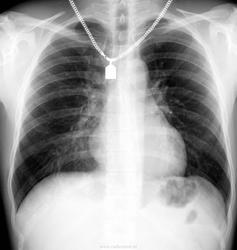

Случай 2.

Молодой человек 30 лет. Проводил ц ФГ в 2010 году, после чего был направлен на дообследование (КТ). Сейчас пришел на контроль, протокол КТ предстваил лично.

От бокового снимка отказался...увы. Что скажете?